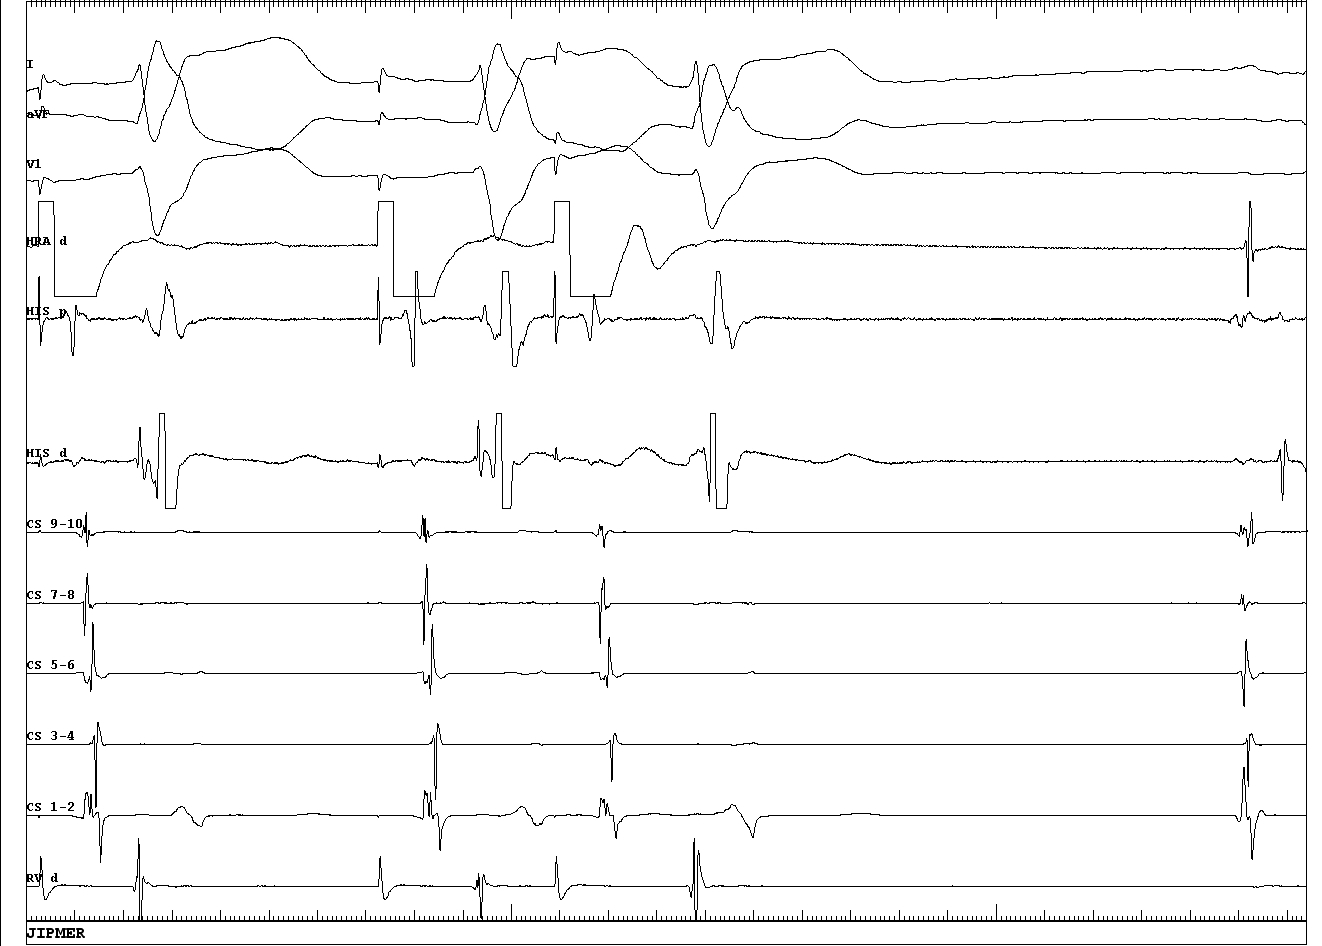

No retrograde conduction through pathway

01_central_VA.JPG

Antegrade conduction is decremental

02_decremental_antegrade.JPG

Retrograde His activation with short, fixed VH

03_VH_change.JPG